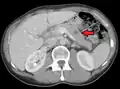

CT image of multiple liver metastases -